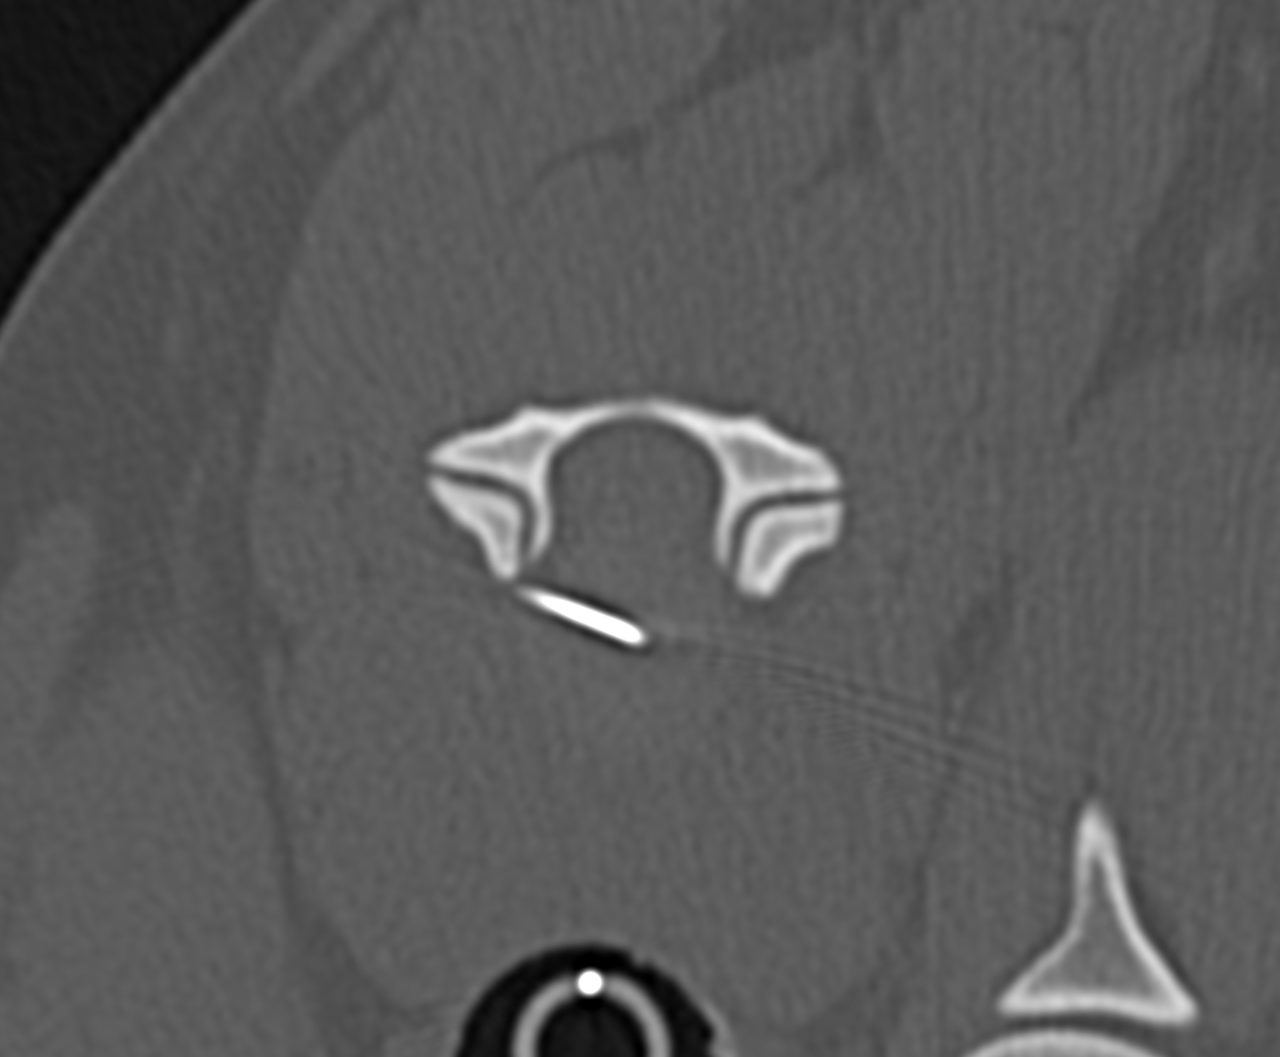

10歳のイタグレさんが四肢不全麻痺になっているので、精査希望で来院されました。MRIではC4~C5,C5~C6、の中程度のIVDDが確認されました。今回は経皮的椎間板レーザー除圧術(PLDD)により対応しました。ニードルを外科イメ誘導下で椎間板に穿刺し、穿刺部位はCTで確認し、問題なければそのままレーザーファイバーを挿入し、蒸散を行います。この手技は今まで外科的に適応されなかった多発性の椎間板ヘルニアにも低侵襲アプローチが可能となります。しかし、即効性はないため鎮痛剤を使いながら経過観察を行います。